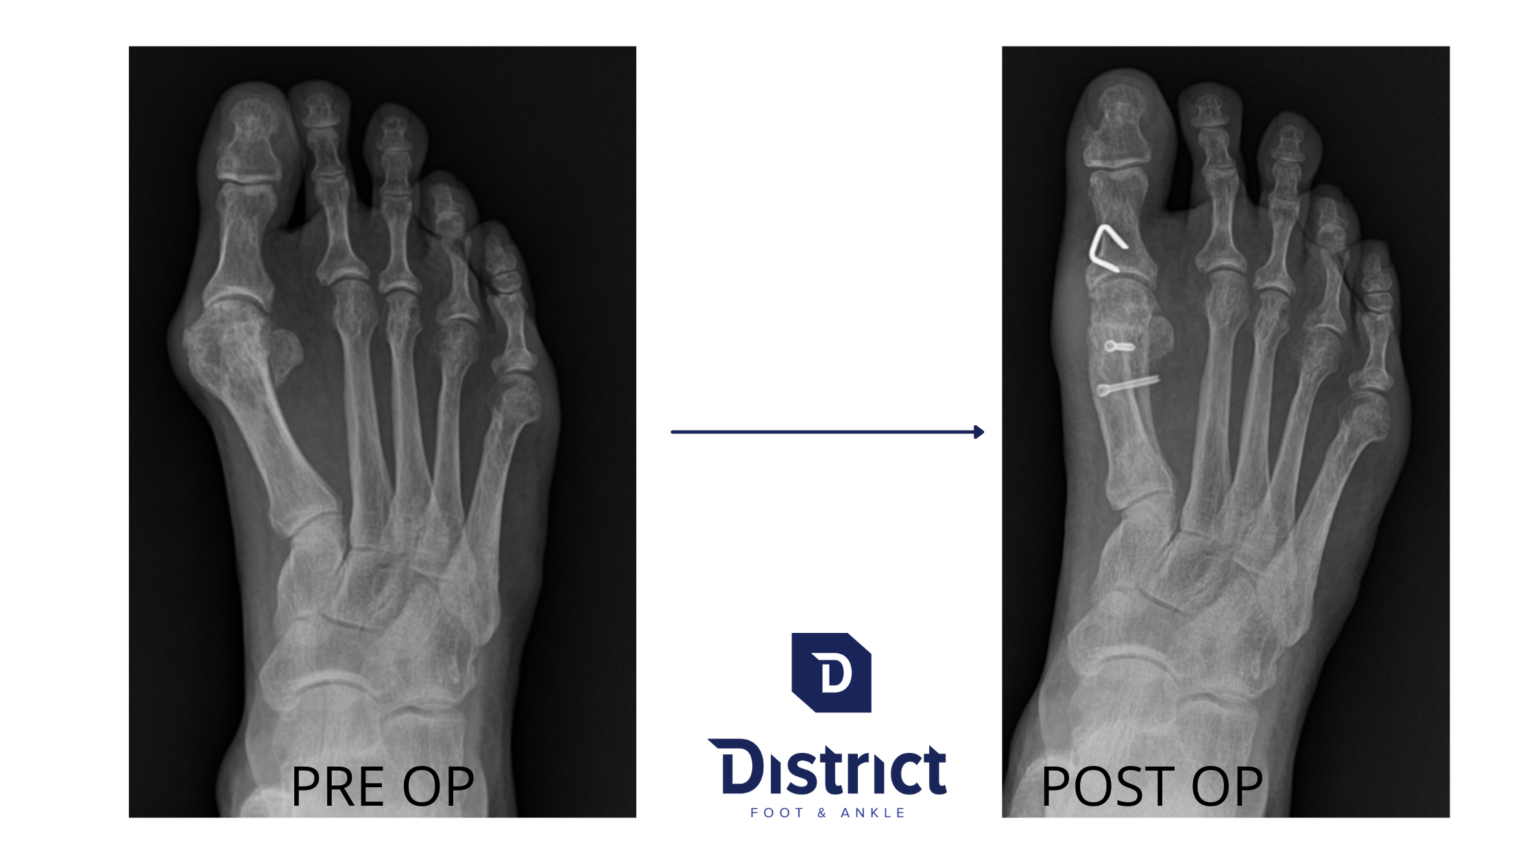

From districtfootankle.com

Foot Bunion Treatment Surgery Doctor Alexandria, Northern VA Foot Bunion Va Rating Veterans guide can help you understand how a bunions va disability rating is determined and what benefits you may be eligible to receive. Learn how to get va disability compensation for bunions, a bony bump on the base of the big toe, caused by service or other factors. See the diagnostic codes, rating criteria, and monthly payments for each condition.. Foot Bunion Va Rating.

Bunion Surgery Alexandria VA Foot Doctor Foot Bunion Va Rating Find out how to prove service connection, submit evidence, and get rated for your foot condition. Veterans guide can help you understand how a bunions va disability rating is determined and what benefits you may be eligible to receive. See the diagnostic codes, rating criteria, and monthly payments for each condition. Learn how to get va disability compensation for bunions,. Foot Bunion Va Rating.